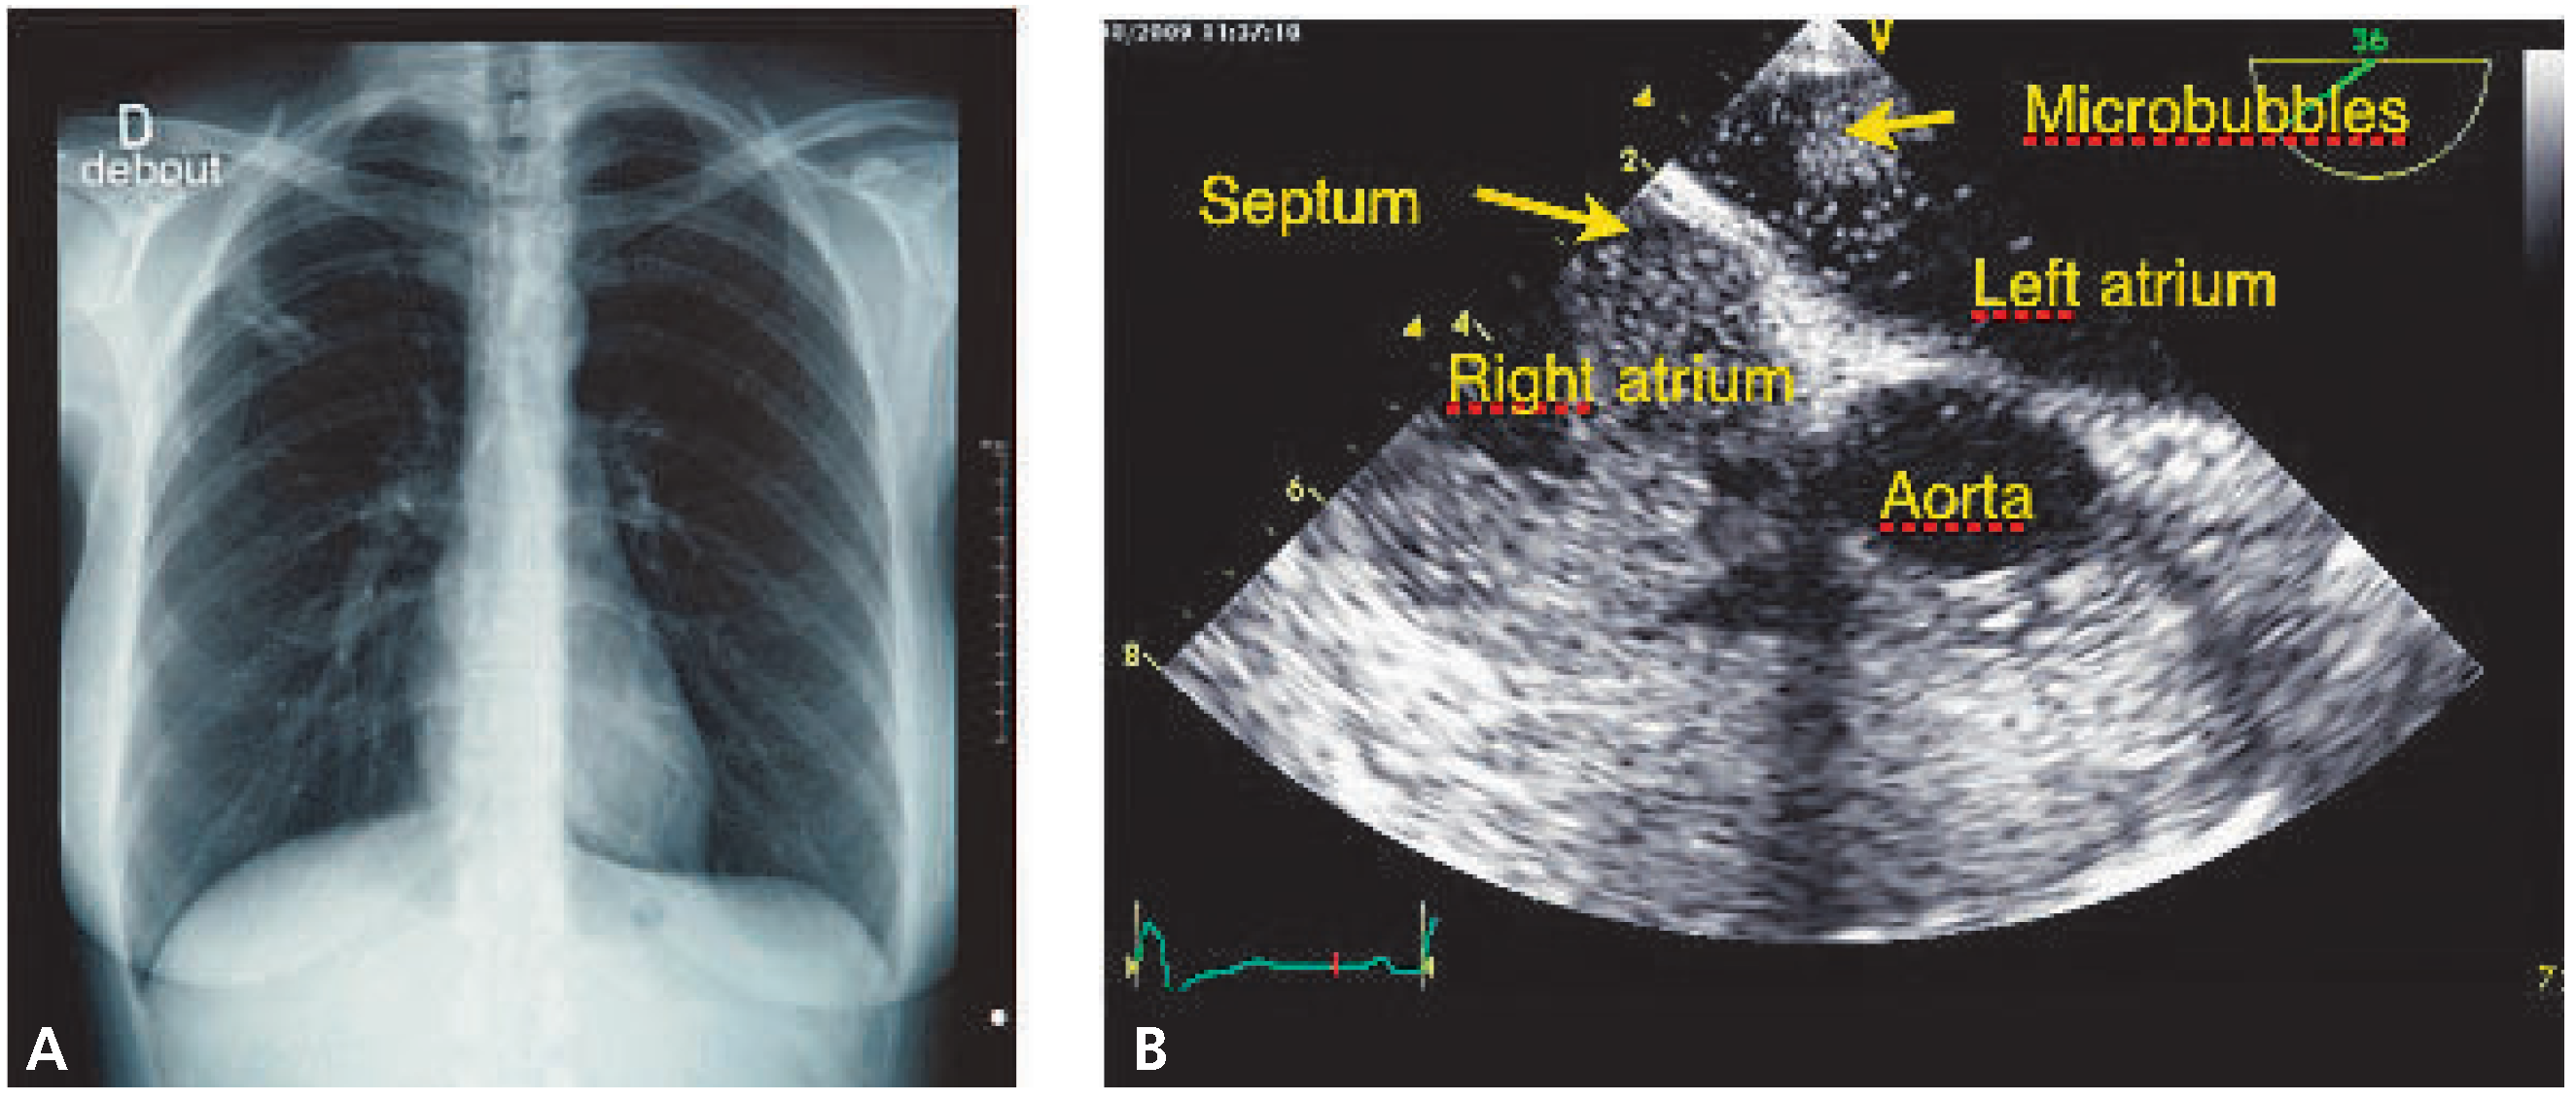

Stroke and Pulmonary Opacity